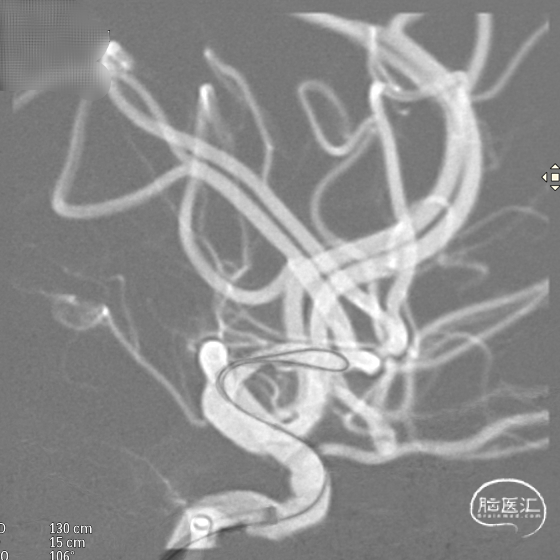

支架到位,远端打开(正侧位):4.75-20mm支架在大脑中动脉M1段打开,回撤至C6段远端锚定。支架释放过程中,轻柔推送支架系统,可见支架导管沿血管壁大弯侧走行,支架打开良好。

输送导丝及微导管回撤:释放至支架末端,减张系统,回撤支架导管,释放支架。沿支架推送杆,调节系统张力,将支架导管通过支架到达C7段。

支架内使用成襻微导丝进行按摩,使支架充分贴壁。

术后造影:支架覆盖两枚动脉瘤瘤颈,贴壁良好,瘤体内可见造影剂滞留。

术后支架显影: